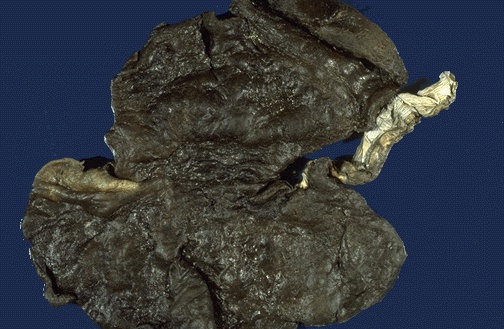

Ingestion of acids and alkalies produces severe mucosal damage. Alkalies (lye) are worse and usually produce ulceration that extends into and through the muscular wall of esophagus and/or stomach.Here, a patient swallowed sulfuric acid. The acid charred the gastric mucosa. |